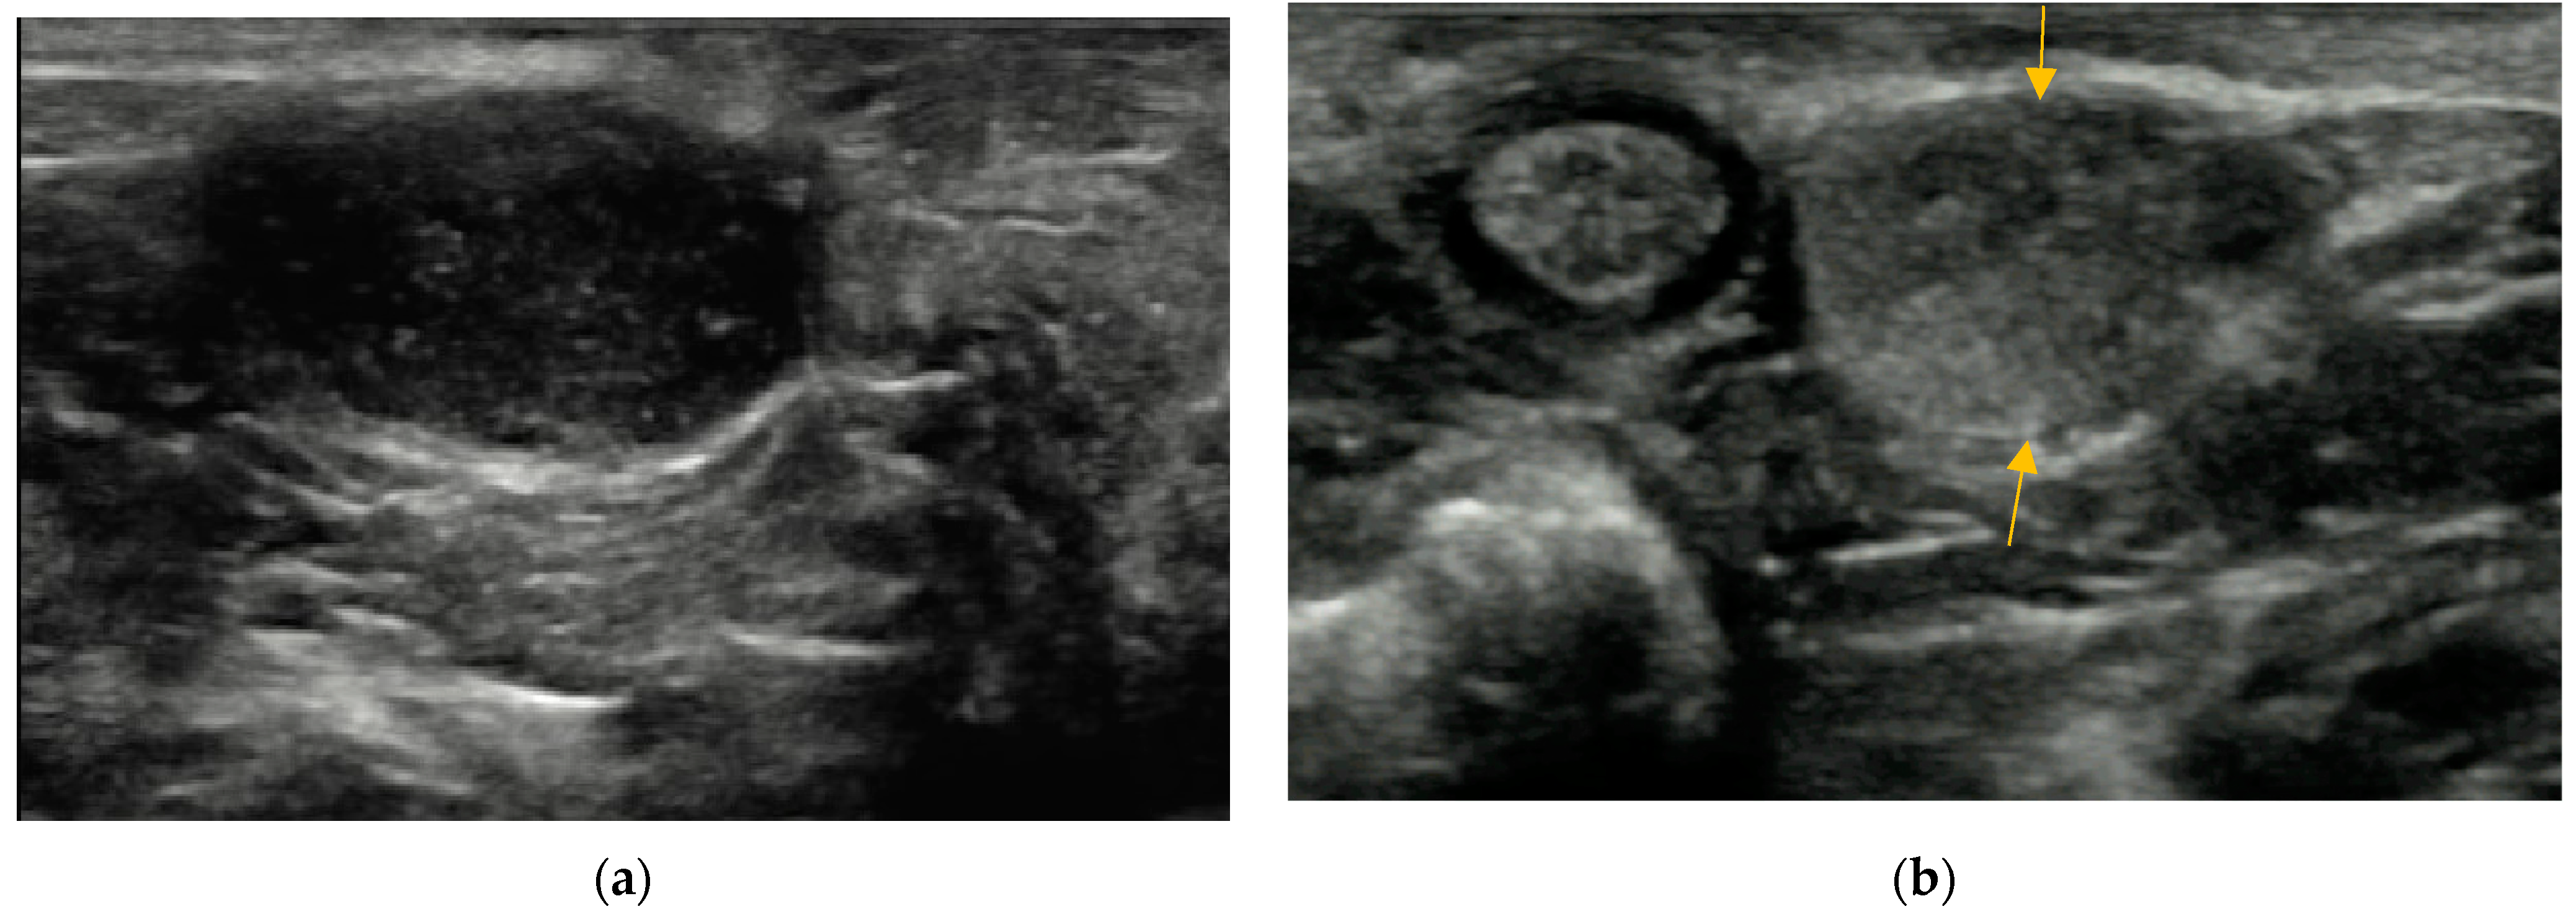

2.4.3. Wall of Anal Sacs

3.4. Wall of Anal Sacs

3.5. Adverse Findings